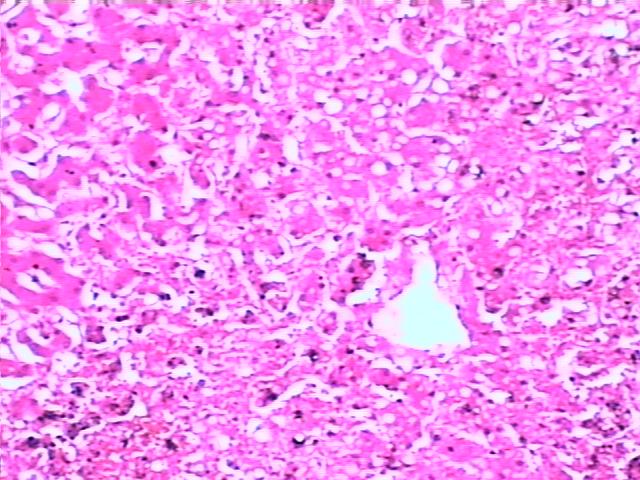

肺褐色硬化 brown induration of lung

1.肺泡壁增厚,肺泡壁毛细血管扩张充血

2.部分肺泡腔内含心衰细胞或含铁血黄素(褐色),部分肺泡内有淡红色水肿液

3.部分肺泡壁内可见红染的胶原纤维束(硬化)